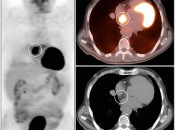

Distinguishing Malignant FDG Uptake from Non-Malignant Uptake:

While most cancers demonstrate significant metabolic activity, FDG uptake is unfortunately not limited to malignancy. Malignant uptake must be distinguished from normal and non-malignant uptake – which is truly the art of reading and interpreting PET/CT scans.

To this end, considerable attention will be made in later chapters to:

- Benign Findings that are FDG-avid [Chapter 6]. [Fig. 4]